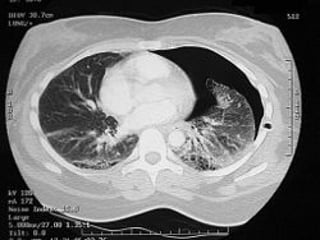

b- la tomodensitométrie thoracique :

   non nécessaire au diagnostic.

   diagnostic étiologique et discussion d’un geste

thérapeutique radical++.

   risque de récidive en précisant: le nombre, le volume

et la topographie des bulles.

b- la tomodensitométriethoracique :  non nécessaire au diagnostic.  diagnostic étiologique et discussion d’un geste thérapeutique radical++.  risque de récidive en précisant: le nombre, le volume et la topographie des bulles.